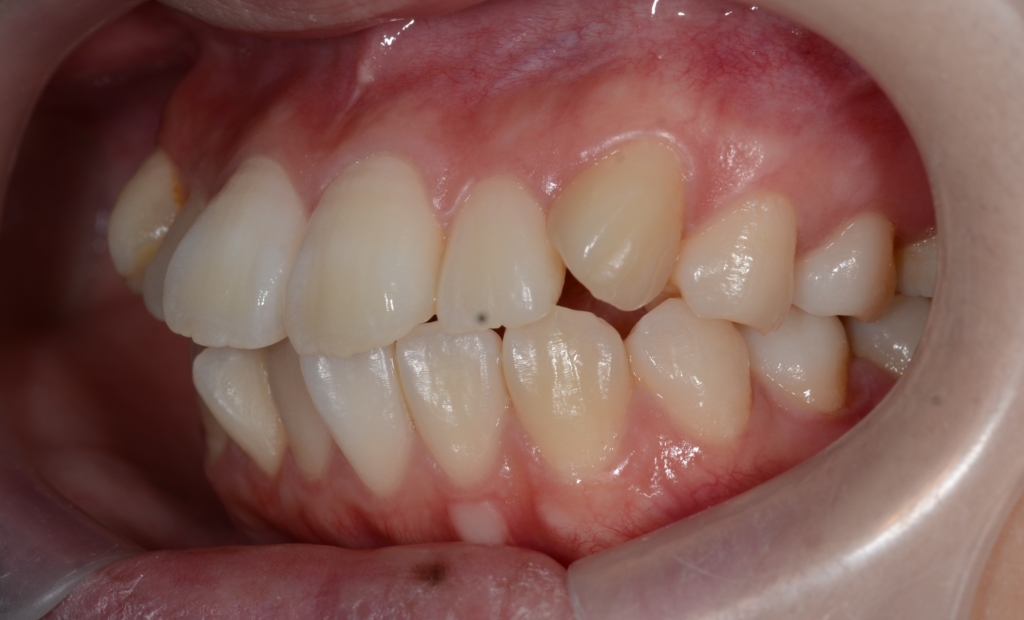

【Before】

#1.歯と顎の不調和による叢生(軽~中等度)

と診断しました。

【治療方針】

1.上下左右の奥歯を1本ずつ抜歯してスペースを作り、前歯の乱れを改善

2.残りのスペース分を使い、上下前歯を可及的に後方へ移動